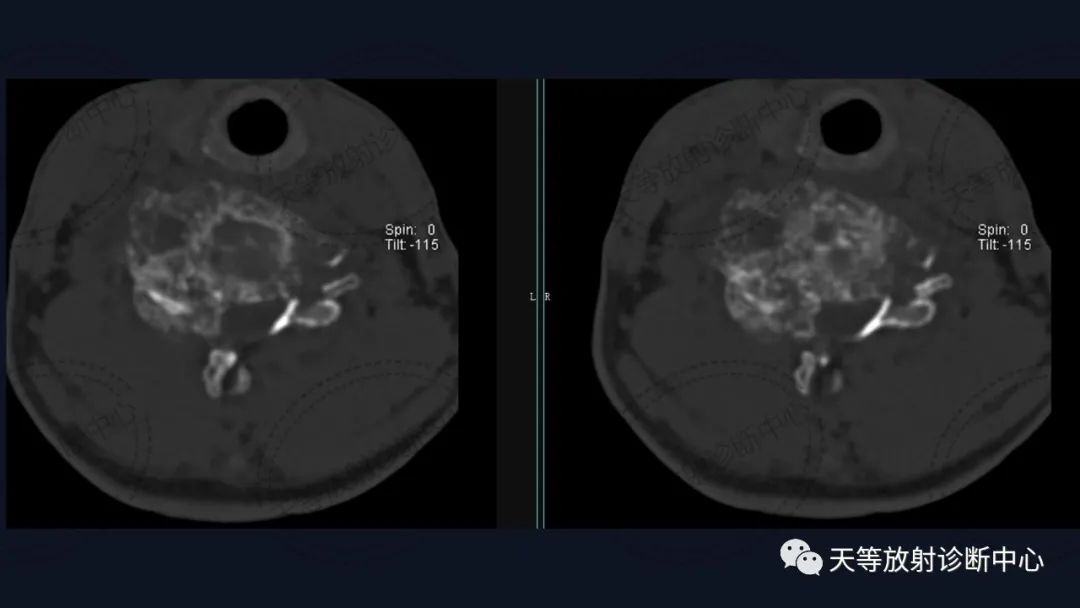

骨质破坏呈溶骨性,大量钙化,肿块向外生长,局部突入椎管内。

肿瘤复发,椎旁分叶状软组织肿块,内部信号不均,混杂信号,高低信号不等,内见线状小叶间隔。

DWI信号较高,内部钙化灶呈散在泥沙样低信号灶。

病例1:上图:软骨肉瘤。CT显示椎管及其附件骨质溶骨性破坏,椎体周围软组织肿块并含大量钙化影,钙化呈斑片状、斑点状不定型。整个肿块外生性生长为主,局部突入椎管内。